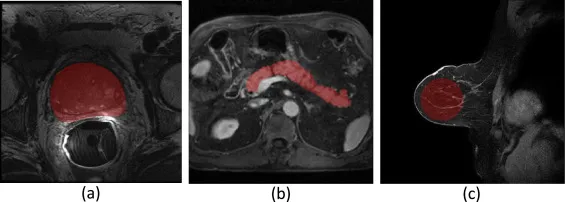

图7.不同MRI数据集的感兴趣区域(ROI)可视化:(a) 前列腺MRI,(b) 腹部MRI,和 © 乳腺MRI。红色区域表示ROI。